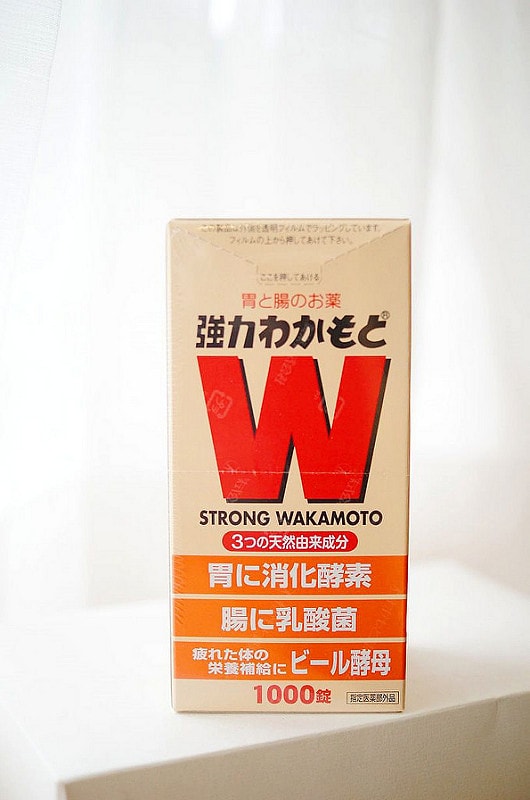

因為我有胃脹氣的問題

就買了一罐WAKAMOTO自己吃吃看

說來慚愧,這是我活了快30年第一次吃

不過對胃脹難消化是還滿有效的!

重點是在日本買跟在台灣買價格真的有落差喔~